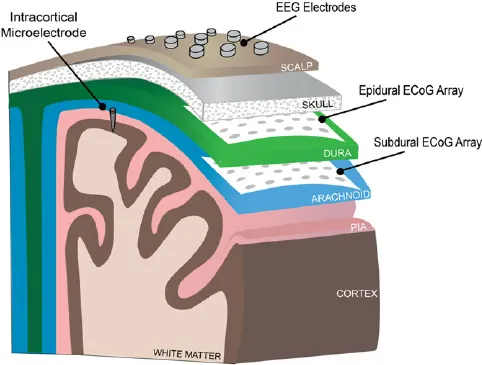

植入位置的选择是脑机接口的一个重要方面,需要仔细考虑技术和医学因素。这里有几个地方可以植入脑机接口,这取决于癌症的阶段,肿瘤的类型等。

皮质内深度电极:这是一种薄型多电极阵列,可植入大脑以记录深层结构的神经活动。它们可用于癌症位于大脑深部的病例。

皮质内深度电极

硬膜下电极:这些电极放置在大脑表面,通常在头骨下方,但在硬脑膜(覆盖大脑的保护膜)上方。它们可以提供高分辨率的神经活动记录。

植入硬膜下电极

硬膜外电极:这些电极放置在硬脑膜的外表面,提供来自大脑最外层的记录。

这张图片显示了每个电极的不同位置: